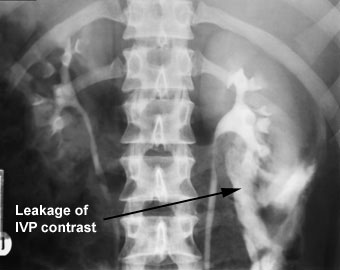

The image on the left is a normal IVP. The image on the right shows an IVP with contrast leak.